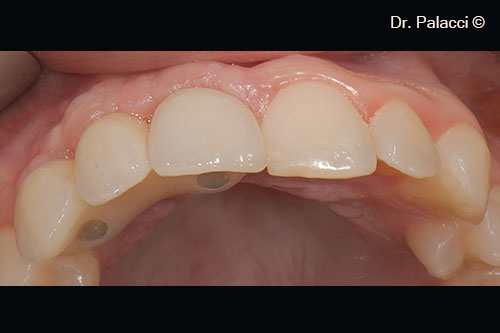

Ca phẫu thuật giai đoạn 2 được thực hiện 4 tháng sau đó. Các trụ cấy ghép vẫn ổn định (ostell 74) và trước khi can thiệp mô mềm (vạt Palacci), GTO được thêm vào vị trí phía trên để tăng chiều cao

Hình ảnh nhìn từ mặt nhai. Hãy chú ý sự gia tăng theo chiều dọc và chiều ngang của mô

Hình ảnh nhìn từ phía trước. Hãy chú ý sự gia tăng theo chiều dọc và chiều ngang của mô